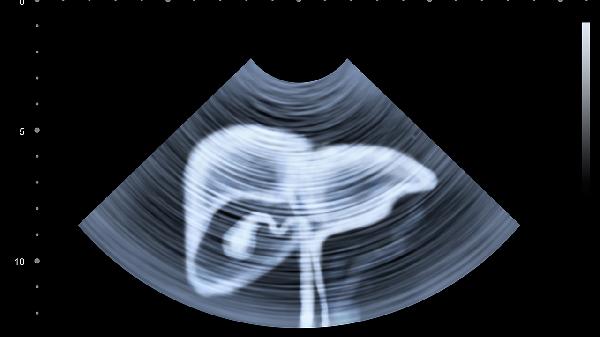

肝癌介入手术后恶心是正常的术后反应,可能与麻醉反应、药物刺激或手术创伤有关。

肝癌介入手术属于微创治疗,但术中使用的化疗药物、栓塞剂或造影剂可能刺激胃肠黏膜,引发恶心症状。部分患者对麻醉药物代谢较慢,术后24-48小时内可能出现头晕恶心等反应。手术过程中导管对血管的机械刺激也可能通过神经反射引起胃肠道不适。这类恶心通常程度较轻,术后2-3天会逐渐缓解,期间可通过静脉补液维持水电解质平衡,医生会根据情况使用盐酸昂丹司琼注射液等止吐药物。

若术后恶心持续超过3天或伴随频繁呕吐、腹痛腹胀、发热等症状,需警惕肠梗阻、肝功能异常或感染等并发症。此时需要进行血常规、肝功能及腹部影像学检查,排除胆道感染、腹腔积液等病理情况。对于合并肝硬化的患者,术后恶心可能与门静脉高压加重有关,需要监测血氨水平预防肝性脑病。